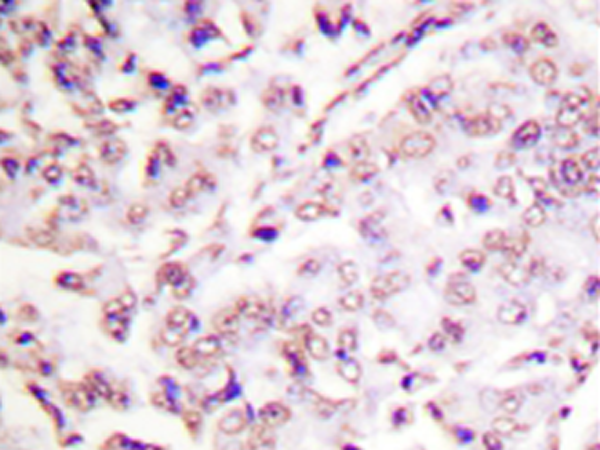

IHC positive control: |

Human breast carcinoma tissue |

IHC Recommend dilution: |

50-100 |